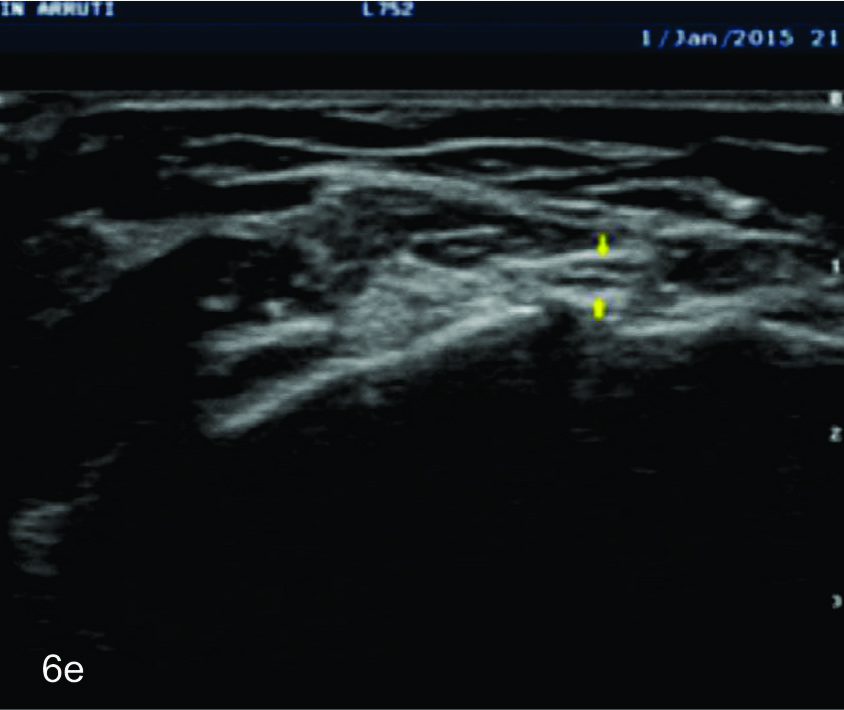

Figura 6

Nervio cubital

B- tercio medio del brazo,

C- tercio distal del brazo,

D- codo en canal epitrocleo-olecraneano,

E- codo- canal cubital,

F- tercio proximal antebrazo,